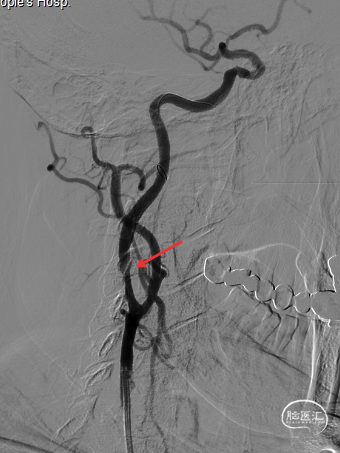

➢ 脑血管造影检查

保护伞到位后释放(左图箭头),2.5*20mm通桥白驹®球囊以6atm扩张(右图箭头)。

扩张完毕后多角度造影显示狭窄较前明显改善(箭头处)。

撤出保护伞观察10分钟复查造影,无弹性回缩,狭窄明显好转,血流明显改善(箭头处),结束手术。